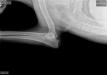

OFA hips and elbows 11.13.18 : SG1 Pyro vom Julianenweg OFA good hips normal elbows 2019 Green Mountain Iron Dog